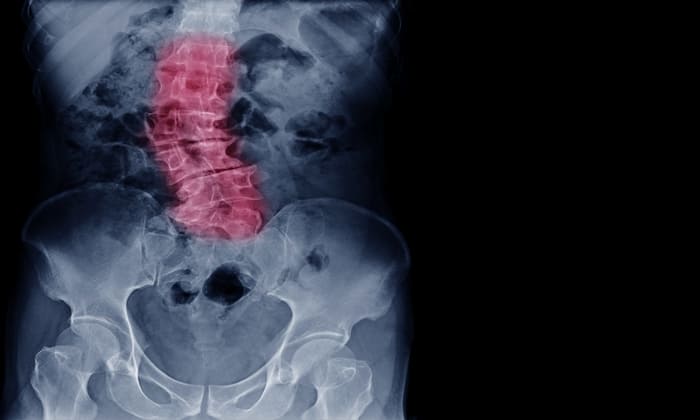

กระดูกสันหลังคด (Scoliosis) หมายถึง ภาวะที่กระดูกสันหลังโค้งผิดปกติ โดยปกติแล้ว กระดูกสันหลังของเราจะวางตัวในแนวตรงแบบเอียงเล็กน้อย แต่คนที่เป็นโรคกระดูกสันหลังคดจะมีแนวกระดูกสันหลังที่โค้งงอมากผิดปกติ ทำให้กระดูกสันหลังมีลักษณะเป็นรูปร่างโค้งคล้ายตัว C หรือ S

อาการคดโค้งผิดปกตินี้ สามารถเกิดขึ้นได้กับแนวกระดูกสันหลังทุกส่วน แต่ส่วนใหญ่มักปรากฏบริเวณกระดูกสันหลังส่วนบนและกระดูกสันหลังส่วนล่าง หรือบริเวณเอว